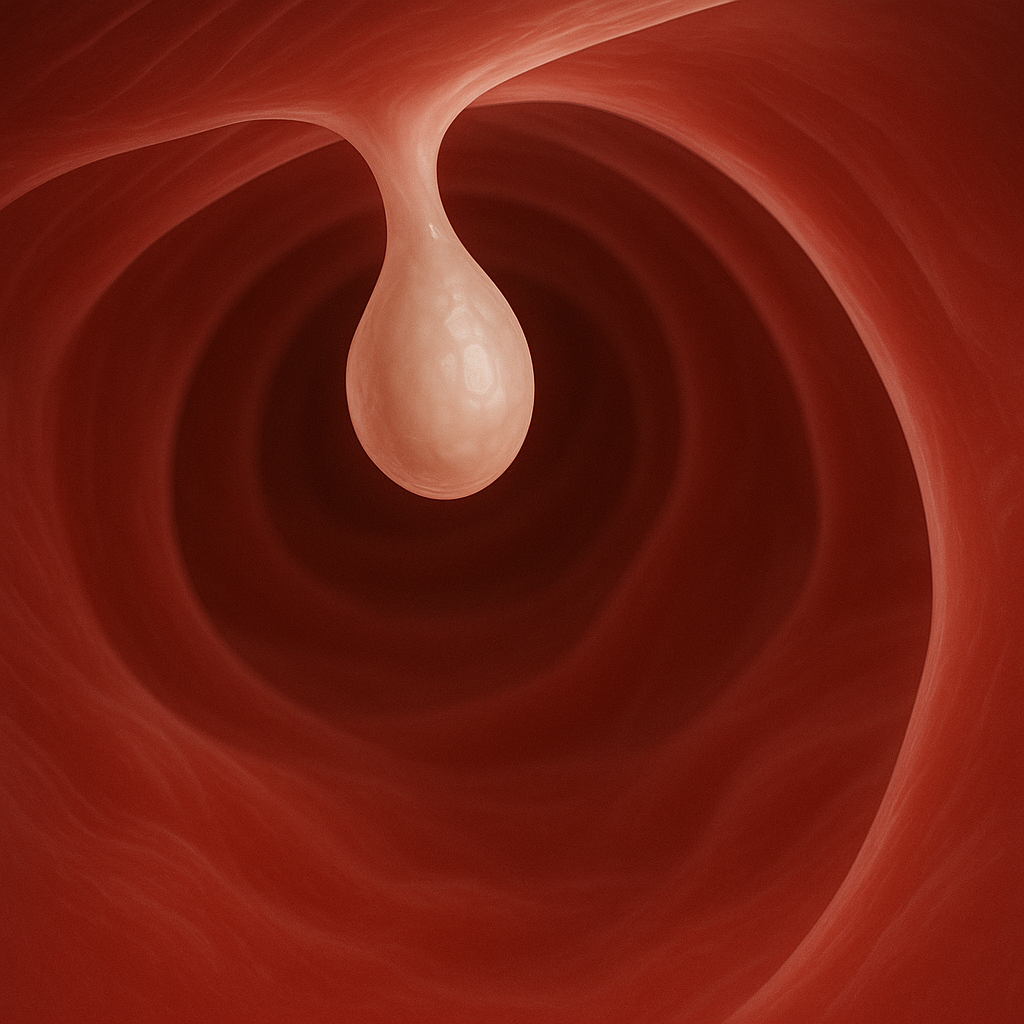

건강검진 항목 중 ‘대장내시경’은 많은 사람들이 꺼리는 검사 중 하나다. 검사 전 장 정결제를 복용해 장을 비워야 하는 등 절차가 번거롭기 때문이다. 하지만 최근 20~40대에서도 대장암 발병률이 눈에 띄게 증가하며 조기 검진의 중요성이 커지고 있다.

순천향대 부천병원 대장항문외과 박나현 교수는 “대장암은 주로 60세 이상 남성에게 흔히 발생하지만, 50세 이하 젊은 환자 비율도 최근 30년간 80% 이상 증가했다”며 “20~49세 젊은 연령층에서도 발병률이 계속 높아지고 있으며, 이는 조사 대상 42개국 중 가장 높은 수준”이라고 설명했다.

박 교수는 “젊은 환자에게 발생하는 대장암의 성질은 더 공격적일 가능성이 있어 조기 진단과 치료를 받는 것이 중요하다”며 “가족력이 있는 경우에는 더 젊은 나이부터 대장내시경을 받는 것을 추천한다”고 했다.

대장암을 예방하는 방법 중 가장 중요한 것은 식습관이다. 섬유질이 풍부한 채소와 과일을 충분히 섭취하고, 가공육과 기름진 음식 섭취를 줄이는 식습관이 필요하다. 또한 규칙적인 운동, 금연, 절주가 대장암 예방에 도움이 된다. 국내에서는 분변잠혈검사가 선별검사로 시행되고 있지만, 대장내시경을 최소 5년에 한 번 받는 것이 더 효과적인 예방법이다.